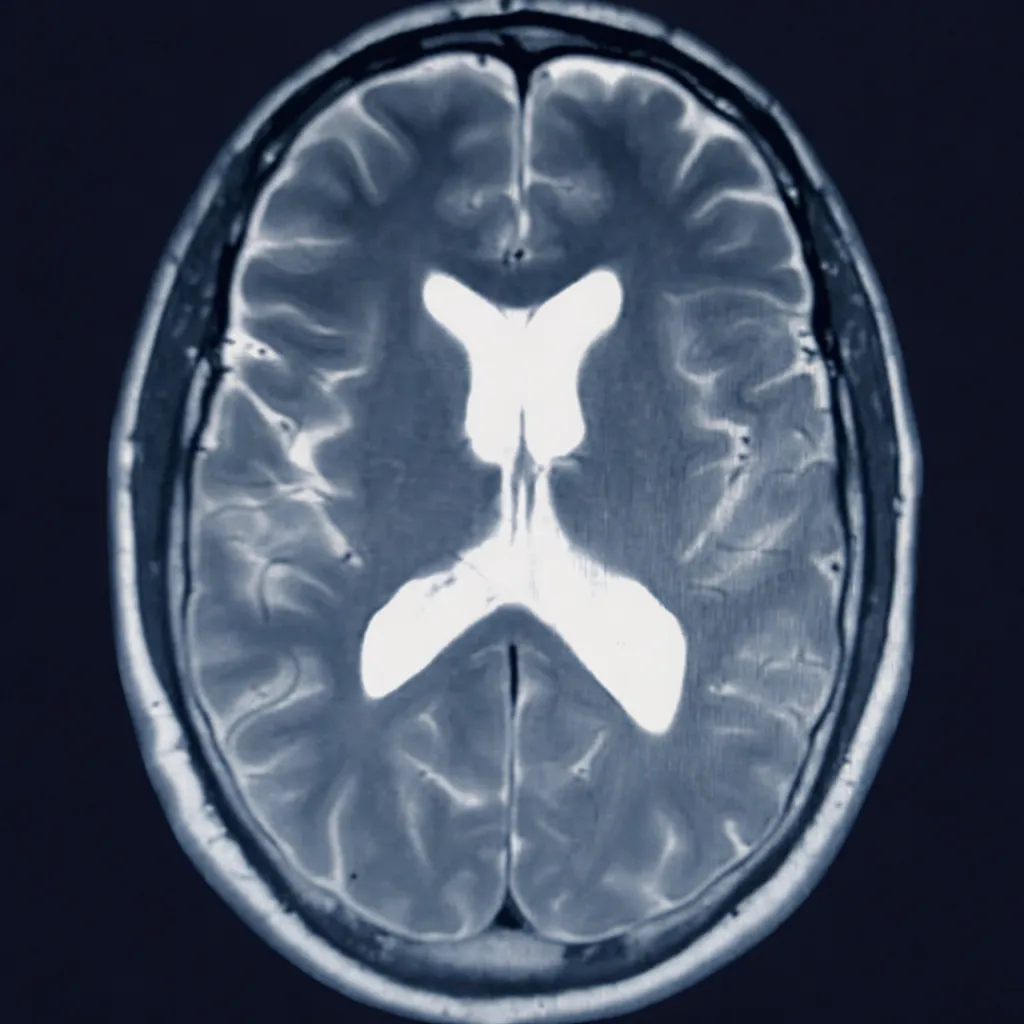

AI-Enhanced Cognitive Assessment

Brain Injury Analysis & Documentation

Platform analyzes brain imaging findings, correlates cognitive test results, and tracks symptom progression—all validated by board-certified physicians to support treatment planning and medical-legal documentation needs.